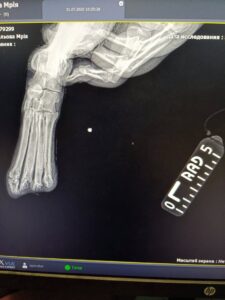

До дніпровського притулку “Вірність” військові передали собаку на ім’я Мрія. У неї відрубані всі чотири лапки та хвіст. Незважаючи на надзвичайний біль і страждання, тварина з довірою дивиться на людей і прагне жити.

На трьох лапках собака зможе опиратися — там відсутні лише пальці. Але для однієї задньої лапи протез — життєва необхідність.